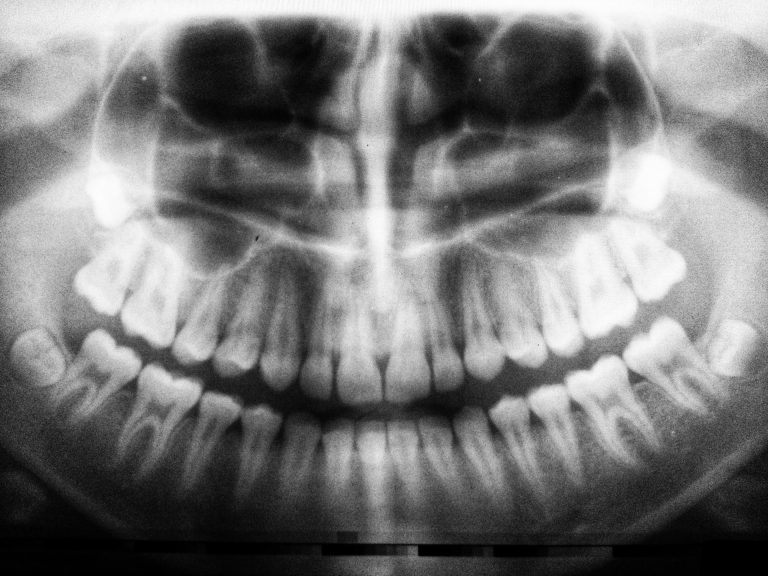

For years, dental x-rays have been used to diagnose oral health complications and detect decaying or damaged teeth. …